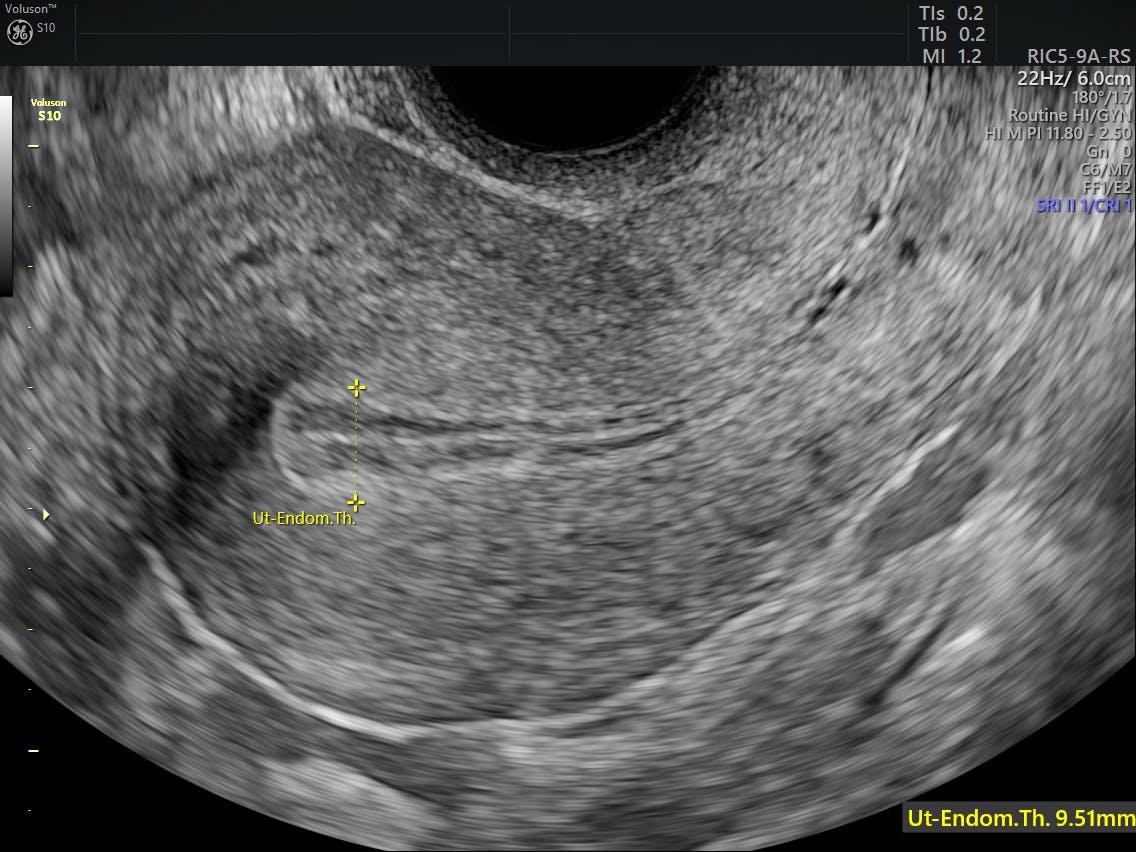

Significance of endometrial thickness on transvaginal sonography in ...

endometrial thickness

A thickened endometrium in a post menopausal patient can be due to a variety of causes. The lining varies based on the stage in the menstrual cycle. The uterine lining is called the endometrium.